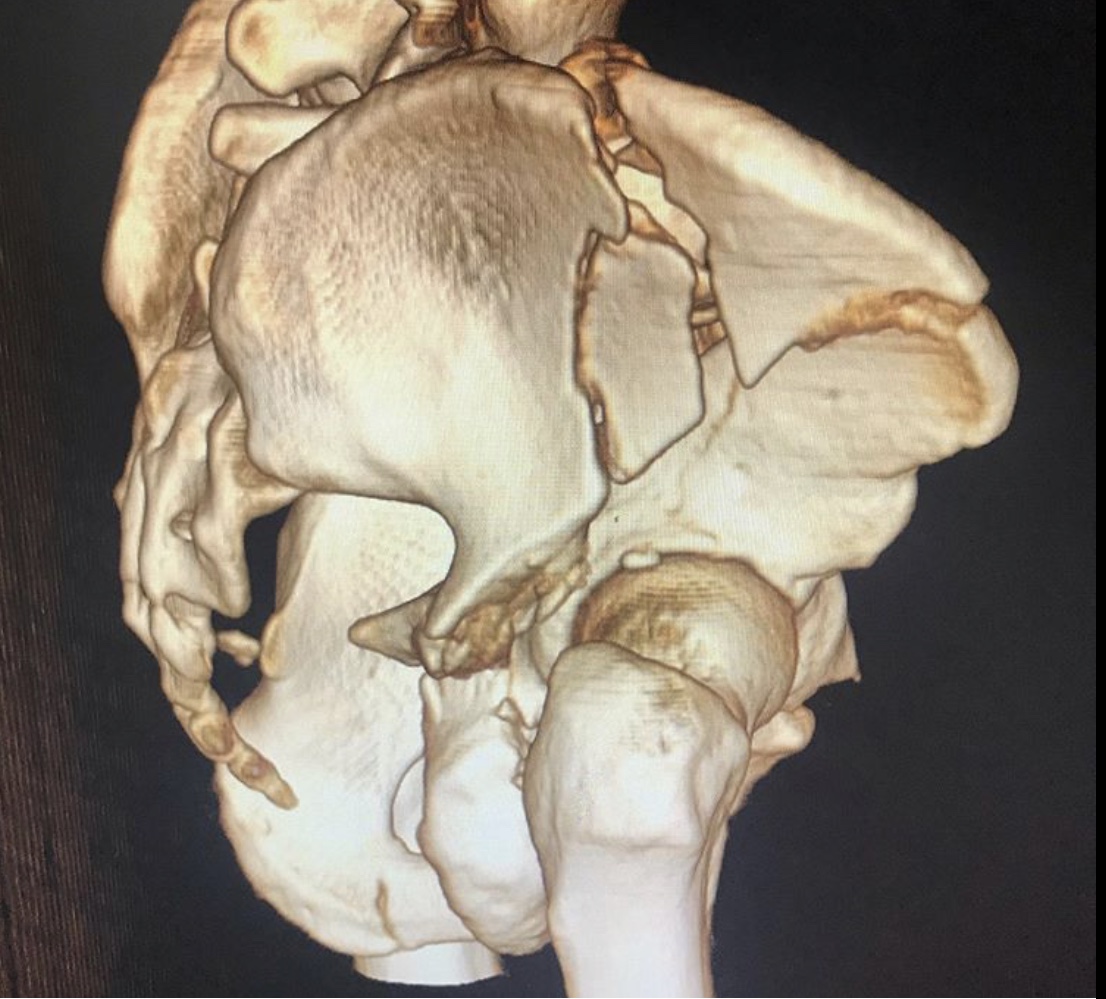

Перелом таза – тяжелейшая травма костей скелета, уступающая по опасности только травмам позвоночника и черепа. Она отличается особой опасностью, так как ее сопровождают обильная потеря крови и шока. Пострадавшему требуется экстренная врачебная помощь, иначе высок риск гибели. Даже при срочном врачебном вмешательстве не всегда удается спасти пострадавшего, который может погибнуть от кровопотери или осложнений болевого травматического шока.

Но к врачам-травматологам Городской клинической больницы № 7 Казани этот пациент поступил лишь спустя месяц после травмы. Врач – травматолог клиники Руслан Закиров признается: «Они в другом городе лечились. Жизнь спасали. К сожалению, не во всех больницах есть возможности для хирургии таза».

Пациента, что называется, «собрали».

Была выполнена открытая репозиция, остеосинтез пластинами.